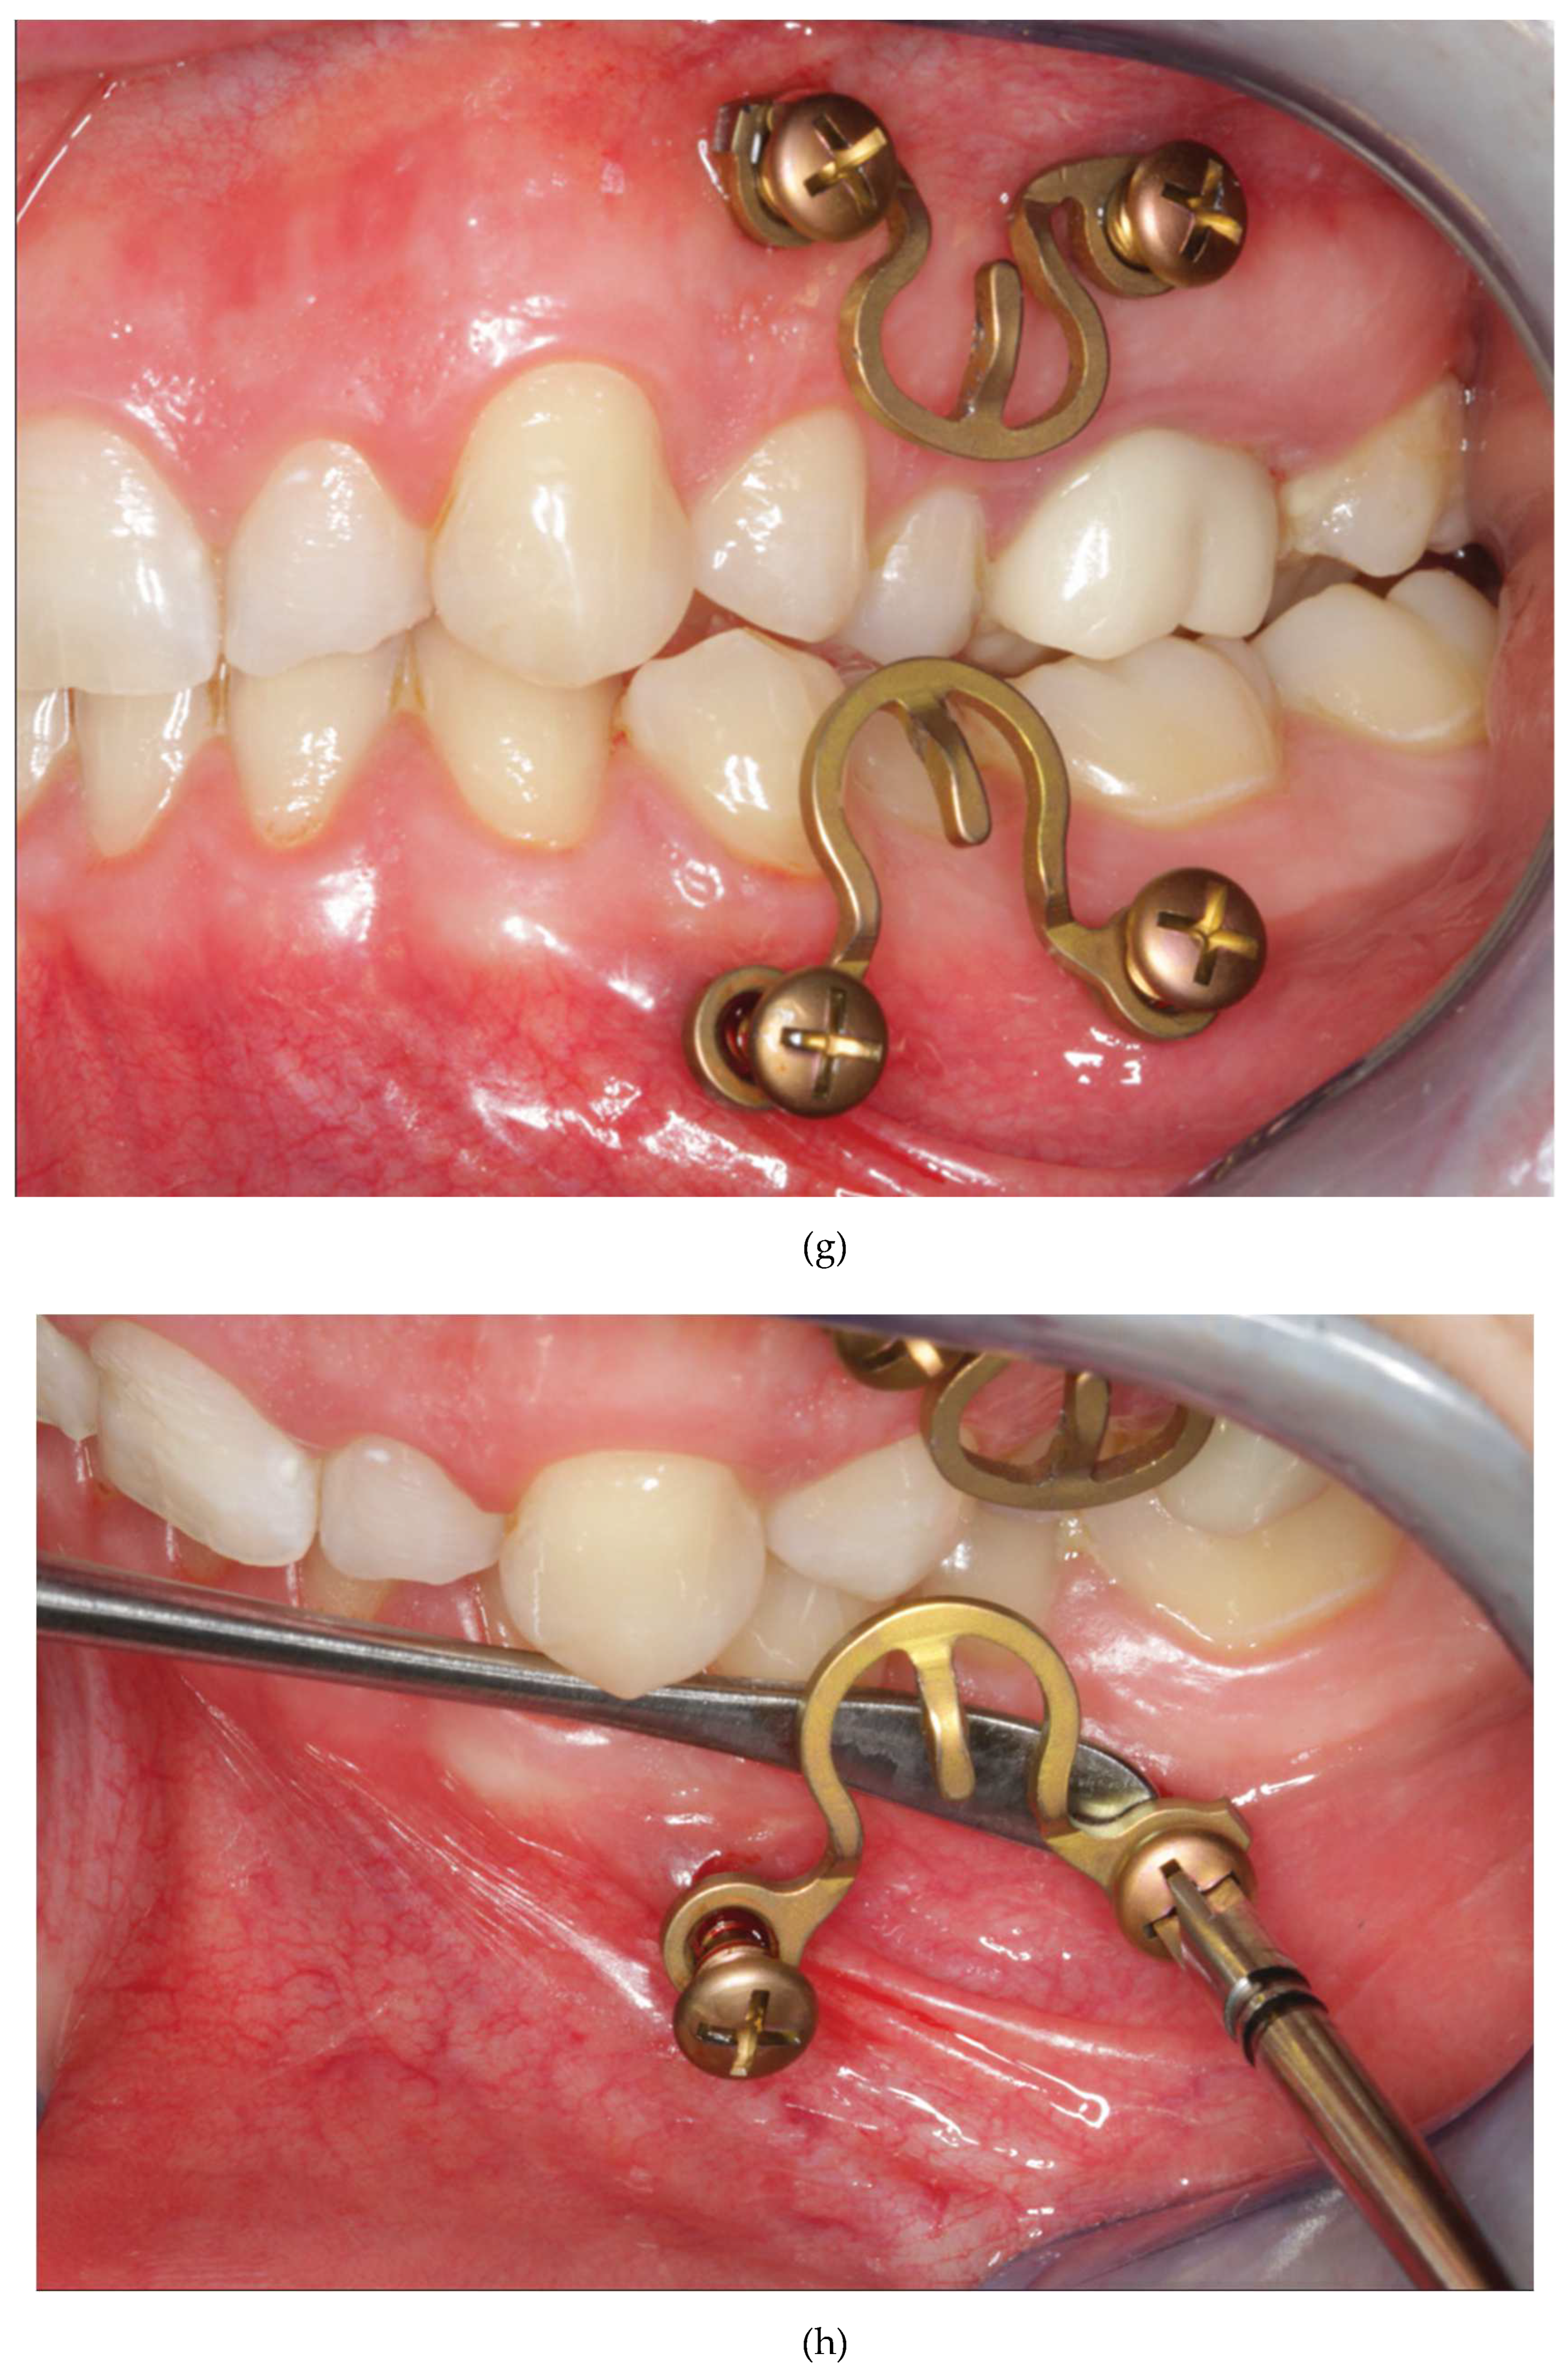

Figure 16.

Figure 16 A: Case with a double mandibular fracture – right mandibular angle; left condylar base (see panoramic x-ray in

Figure 16 L ). Deep bite not suitable for conventional tooth borne arch bars. A low profile MWP Omega segment is tried on along the mucogingival transition zone for interradicular screw fixation in the premolar region of the left maxilla. Interferences with the habitual occlusal position and / or articulatory movements must be ruled out.

Figure 16 B: Owing to the more comfortable access the anterior screw is inserted first. Angulation of the screw should be avoided. The conical locking head of the screw should not get engaged into the plate hole prematurely.

Figure 16 C: The posterior screw is turned likewise halfway into the bone for a loose prefixation of the MWP segment.

Figure 16 D: The MWP segment is supported with a Freer elevator as a spacer below the flatbed portion and the screws are tightened alternately until the plate segment is firmly gripped by the locking threads.

Figure 16 E: Screw fixation of MWP segment completed. Most of the time the conical locking head cannot be fully countersunk in the plate hole. It is essential, however, that the threads of the plate hole and the locking threads of the screw effectively purchase.

Figure 16 F: High profile MWP Omega segment adapted to the interradicular spaces in the premolar region of the opposite jaw, in this case the left mandible. Interferences with the habitual occlusal position and / or articulatory movements must be ruled out.

Figure 16 G: Prefixation – plate segment still moveable.

Figure 16 H: Posterior screw turned into the plate hole, supporting the plate with a Freer elevator from underneath.

Figure 16 I: Anterior screw turned in, while plate segment is supported with Freer elevator - alternate tightening of the screws.

Figure 16 J: MWP segment finally fixed in juxtaposition to the vestibular tooth crowns just below occlusal plane. A steep canine guidance, however, averts disruptive contacts between the second upper premolar and the top rail of the plate.

Figure 16 K: MWP Omega segments mounted in all jaw quadrants for temporary intraoperative MMF with wire ligatures to immobilize the mandible. Note: Conical locking heads are partially countersunk, only.

Figure 16 L: Postoperative Panoramic x-ray after transoral ORIF (miniplate osteosynthesis). 4 MWP segments left in place for optional functional treatment during follow-up. All screws for MWP attachment located in interradicular alveolar bone Inset: four MWP Omega segments as oriented and used in this illustrative case.

Source/origin of Figure 16 A – L : Photograph collection – C.P. Cornelius